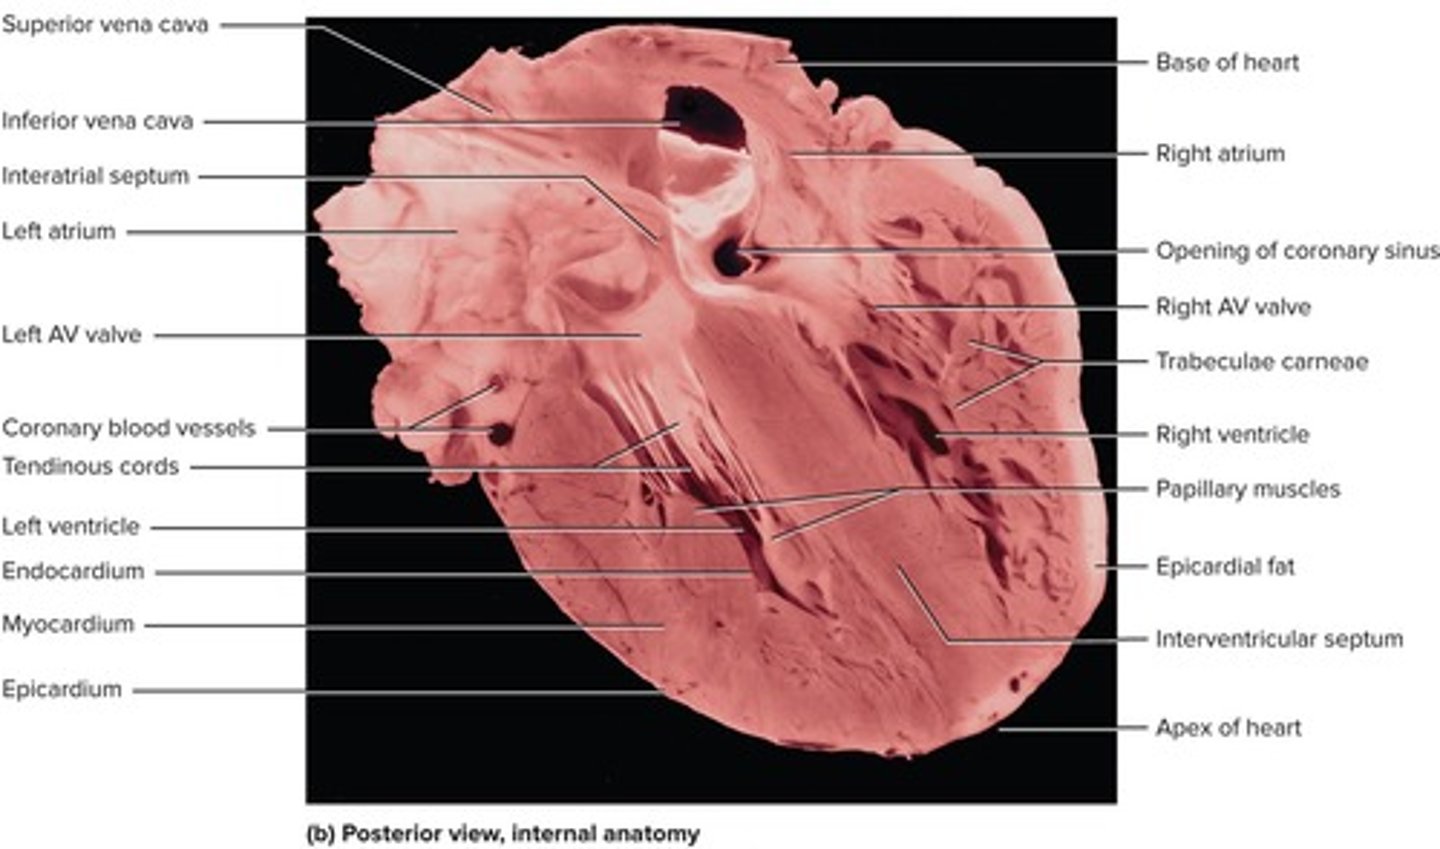

What are the four chambers of the heart?

Right atrium, left atrium, right ventricle, and left ventricle.

What separates the right and left atria?

The interatrial septum.

What is the myocardium?

What are the two layers of the serous pericardium?

The parietal layer and the visceral layer (epicardium).